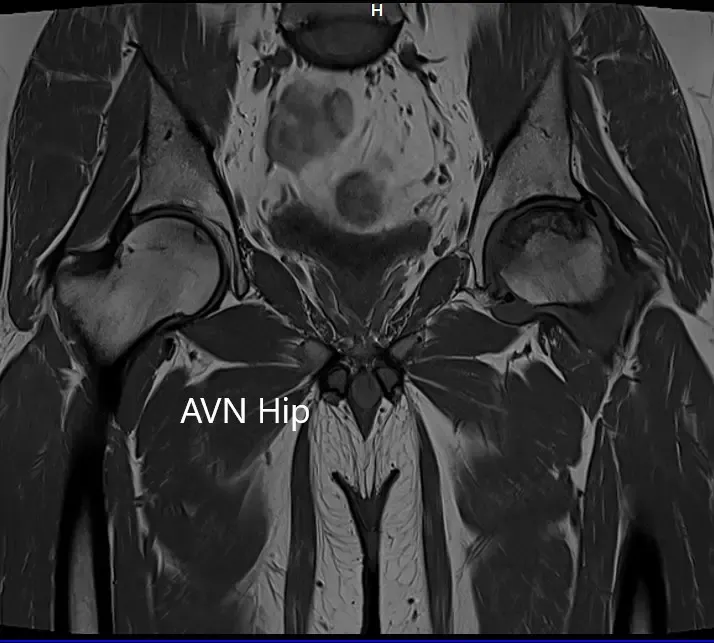

Imaging studies obtained in the form of an X-Ray suggested sclerosis of the left head of the femur. There were marked acetabulum changes. An MRI was further obtained suggesting avascular necrosis of the superior lateral head of the femur with changes in the acetabulum. There was marked hypointense areas on both T1WI and T2WIs.

T1WI coronal section of MRI showing AVN hip.